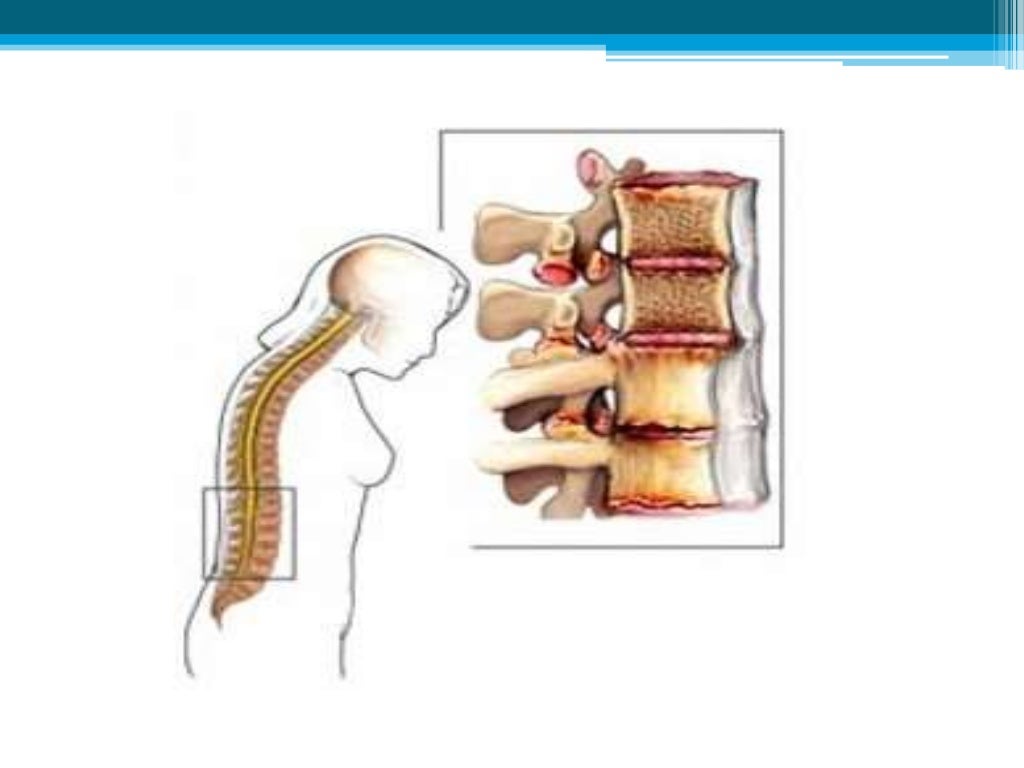

Qué Tan Grave Es La Espondiloartrosis, ¿Qué es la espondiloartrosis y cuál es su tratamiento, 11.47 MB, 08:21, 384,827, FisioOnline, 2016-09-04T10:29:46.000000Z, 3, Pin en articulaciones / huesos, www.pinterest.com.mx, 1280 x 720, jpeg, WebLa espondiloartrosis puede ser potencialmente grave y puede limitar la movilidad de la columna. Los síntomas pueden variar desde un dolor leve hasta un dolor intenso.. WebLa espondiloartrosis o artrosis de la columna vertebral es una enfermedad degenerativa de los cartílagos de las articulaciones que puede afectar a la zona. WebLa espondiloartrosis es un tipo de artrosis que afecta a la columna vertebral, en la que las vértebras, los discos y el cartílago se deterioran. Al deteriorarse el cartílago, las., 20, que-tan-grave-es-la-espondiloartrosis, Novedades y Muebles WebLa espondiloartrosis puede ser potencialmente grave y puede limitar la movilidad de la columna. Los síntomas pueden variar desde un dolor leve hasta un dolor intenso.. WebLa espondiloartrosis o artrosis de la columna vertebral es una enfermedad degenerativa de los cartílagos de las articulaciones que puede afectar a la zona. WebLa espondiloartrosis es un tipo de artrosis que afecta a la columna vertebral, en la que las vértebras, los discos y el cartílago se deterioran. Al deteriorarse el cartílago, las.

WebLa espondiloartrosis lumbar es la artrosis en la columna, que produce síntomas como dolor intenso en la espalda, causada normalmente por el desgaste de la articulación. No en. WebSi la espondilosis cervical comprime gravemente la médula espinal o las raíces nerviosas, el daño puede ser permanente. Hay un problema con la. WebLa espondiloartrosis es un cambio relacionado con la edad de los huesos (vértebras) y discos de la columna vertebral. Estos cambios a menudo se llaman enfermedad. WebLa espondiloartritis es grave. Pero con las estrategias de adaptación adecuadas y un plan de tratamiento coherente, la mayoría de las personas con la afección viven una vida plena. WebLa Espondiloartrosis o también Artrosis de Columna vertebral es una enfermedad degenerativa que afecta a los cartílagos de las articulaciones, provocando diversas. WebLa espondiloartrosis es una enfermedad degenerativa de la columna vertebral, que puede ser prevenida si se realza lo necesario en el momento indicado Es por esto, que aquí en. WebEl objetivo del tratamiento es aliviar el dolor y la rigidez, y prevenir o retrasar las complicaciones y la deformidad de la columna vertebral. El tratamiento de la espondilitis anquilosante es más exitoso antes de que la enfermedad cause daño irreversible. WebLa espondiloartrosis o artrosis (1) de la columna vertebral, es una patología degenerativa que causa desgaste del cartílago articular de las articulaciones.

WebLa espondiloartrosis, también llamada artrosis lumbar, es una degeneración de los cartílagos de la columna lumbar que genera dolor, rigidez y limitación del movimiento. WebLa espondiloartrosis lumbar se clasifica en cuatro grados, según la cantidad de daño que se haya producido en la columna vertebral. El grado I es el menos grave, y el grado IV es el. WebLa espondiloartrosis es una enfermedad degenerativa de las articulaciones que no presenta clínica hasta que los nervios está afectados y tampoco tiene cura. La.